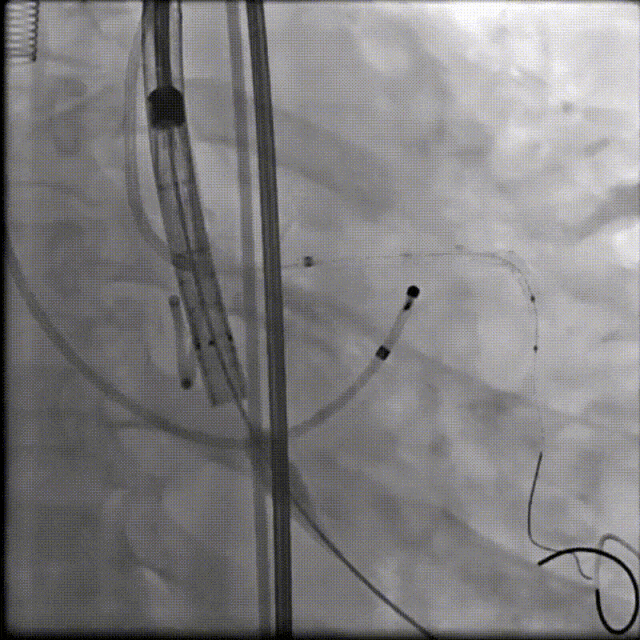

(1)Type 0二叶式主动脉瓣,瓣环适中,中度钙化,Type 0二叶瓣受瓣口形态及钙化影响,瓣架呈非理想椭圆形展开,对瓣架支撑力与顺应性提出了更高要求,同时该病例合并升主扩张,对同轴性和释放的稳定性提出了更高的要求。因此优先选择支撑性和顺应性兼具的瓣膜,以及较柔软花冠的瓣膜,降低对升主动脉的损伤,小锥角的设计进一步提升了瓣膜在释放的稳定性

(2)窦部空间较小,左侧瓣叶冗长,且开口位置在短轴平面,左冠冠脉风险较高,优先选择有收腰设计的瓣膜,降低冠脉风险并保留术后足够的VTC

综合病例解剖特点及患者年纪,决定使用第二代可回收的自膨瓣,可回收提高容错空间,为了降低冠脉阻挡风险,决定采用平衡收腰设计的TaurusElite 的瓣膜,先使用大鞘鞘芯进行预扩,然后上20F大鞘。

麻醉医师:患者本次因间断胸闷3年,再发伴加重2月就诊于我院,拟行经导管主动脉瓣置换术,麻醉选择气管插管全身麻醉,备体外循环,术中密切监测生命体征,维持血流动力学,考虑到冠脉风险,球囊预扩和瓣膜释放之后,严格监测血压和心率的变化。

超声医师:患者为重度主动脉瓣狭窄,术前超声充分评估,心腔大小,心腔容量是否充分,各瓣叶活动程度,该病例左侧冠脉风险较高,工作位以及最终释放超声下充分评估原生瓣叶到左冠侧瓣叶距离,进一步评估冠脉风险。